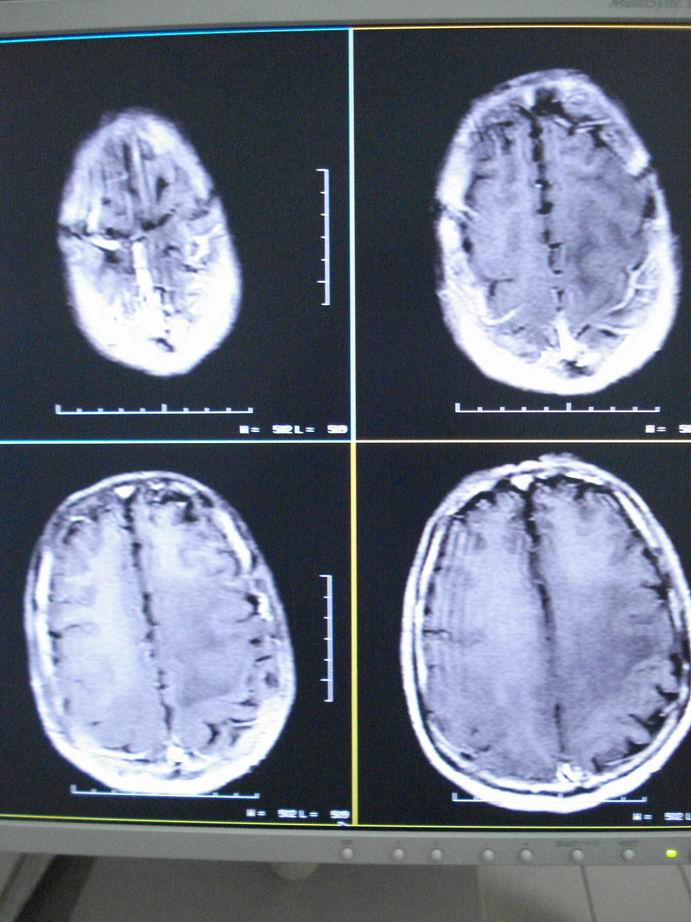

男60岁,左侧肢体乏力及精神异常10天,血压正常,血常规,肝肾功正常,腰穿无异常,请教颅内多发病灶,考虑什么?感染?肿瘤(转移性?)还是其它?

考虑为颅内多发转移瘤

淋巴瘤较转移瘤可能大。

脑内多发占位性病变,首先考虑感染性病变,其次是转移瘤。

结合病人高龄,考虑转移瘤